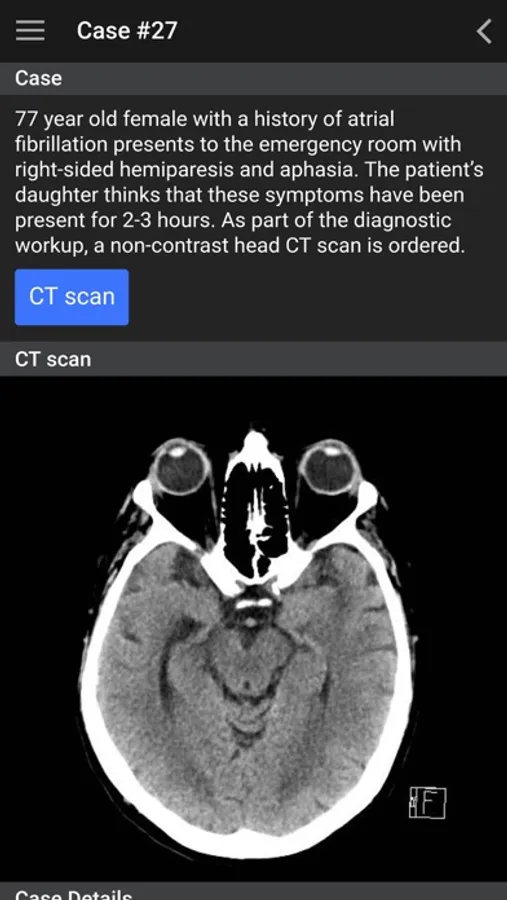

This app is designed for medical trainees and medical professionals to increase their confidence in identifying normal anatomic structures, ordering the most appropriate imaging test and identifying common pathology.

This app is based on the radiology undergraduate curriculum at the University of British Columbia (UBC), which is located in Vancouver, British Columbia, Canada. The app content is organized into the pre-clinical (MS1, MS2) and clinical (MS3, MS4, intern) years. The focus of the pre-clinical years is on identifying normal anatomy and acquiring basic ultrasound skills and the focus of the clinical years is to become familiar with ordering appropriateness criteria and to recognize key pathology. The list of clinical cases presented in this app are developed from the UBC third year medical student clerkship “Must See” clinical objectives.